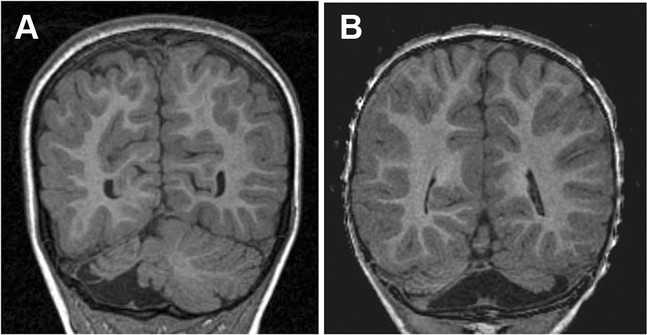

Structural brain damage refers to physical injury or changes to brain tissue that can be seen on brain scans (such as MRI or CT).

In ataxia, this damage most often affects:

🧑⚕️ Diagnosis

Diagnosis usually involves:

- Neurological examination

- Brain imaging (MRI or CT scans)

- Review of medical history and past injuries

- Ongoing monitoring of symptoms

Imaging helps identify where and how much damage is present.